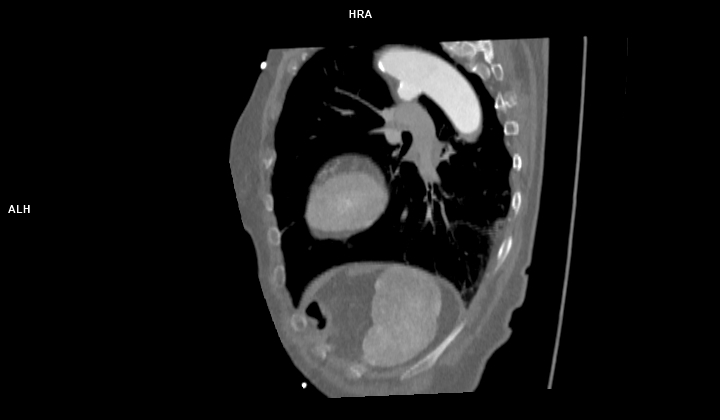

Figurile 1 si 2: reconstrucție multiplanară din achiziție angio în timp arterial – aorta toracică

Discuţie caz nr 102: Ductul arterial este o structura de by-pass între aorta descendentă și trunchiul de arteră pulmonară care funcționează în viață intrauterină deoarece plămânii nu sunt aerați; în mod normal se închide în primele zile după naștere. Imaginile prezentate arată că ductul arterial este închis însă se evidențiază creșterea calibrului unei reminiscențe a ductului arterial la deschiderea în aorta descendentă.

DE LUAT ACASĂ!!! Inserția ductului arterial în aorta descendentă toracică este util să fie cunoscută deoarece dacă avem canal arterial permeabil acesta poate fi de dimensiuni mici și poate să nu cauzeze probleme semnificative rămânând nedetectat – practic descoperire întâmplătoare.